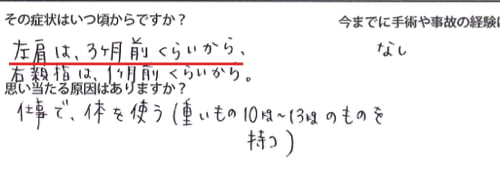

これらの症状は3ヶ月くらい前から・・・

原因はやはりお仕事の頑張りすぎのようでした。

今までの治療履歴は整骨院・整骨院・マッサージなどで

もみほぐし 電気治療などでしたが、すぐに痛みがぶり返す感じでした。